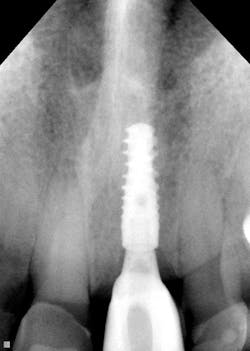

The resolution of DentiMax Open sensors provides 14-16 lp/mm actual, 25 line lp/mm theoretical on size 0 sensor and >20 lp/mm actual, 25 line lp/mm theoretical on the size 1, 1.5, and 2 sensors. Further, Dr. Gordon J. Christensen’s Clinicians Report says that “DentiMax’s sensors exhibited excellent resolution, sensitivity, image quality, and exposure latitude in controlled comparisons with other leading sensor brands.” Quality images are the result with bitewings (figure 9), anterior periapicals (figures 10 and 11), and posterior periapicals (figure 12).